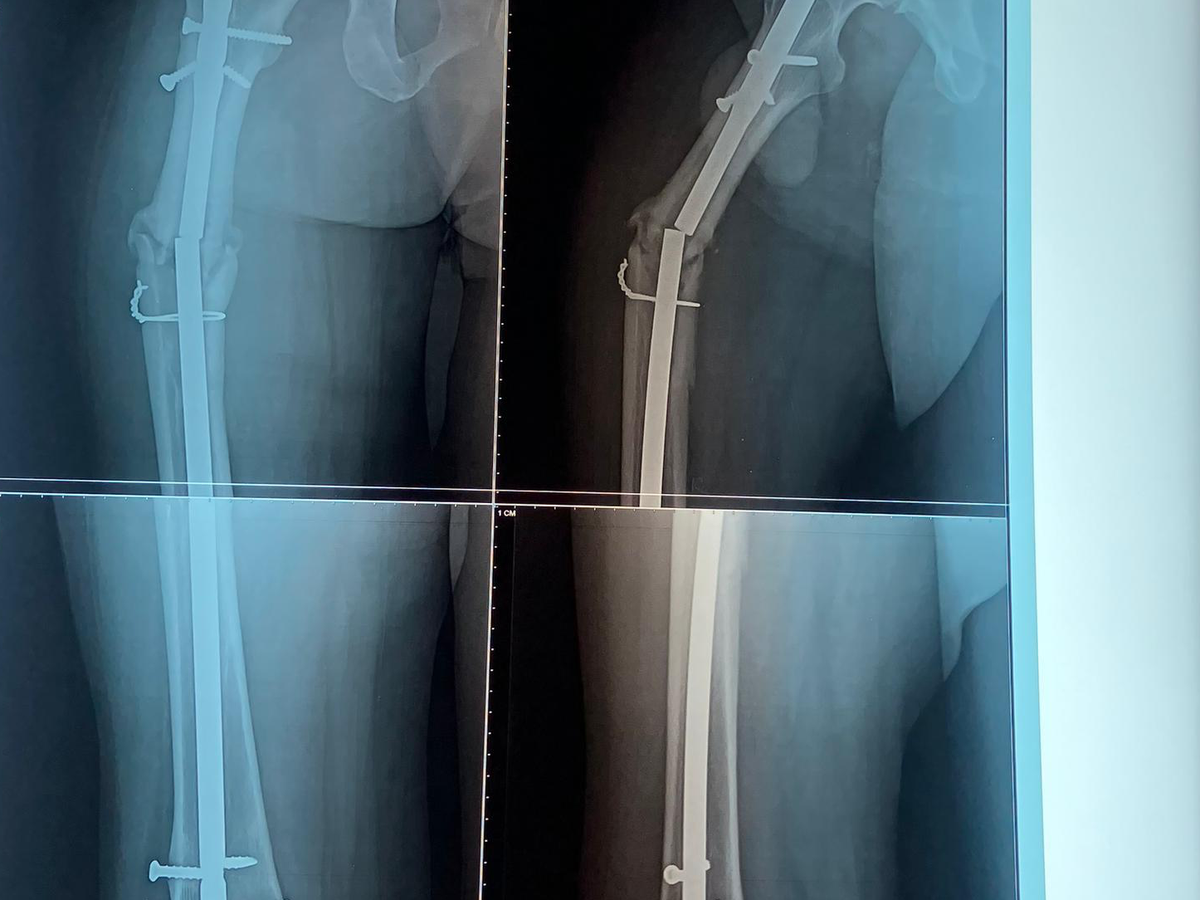

Today, my brother is in unbearable pain. Recent X-rays show that his femur appears broken again. His leg is deteriorating, and without urgent surgery, he may permanently lose it.